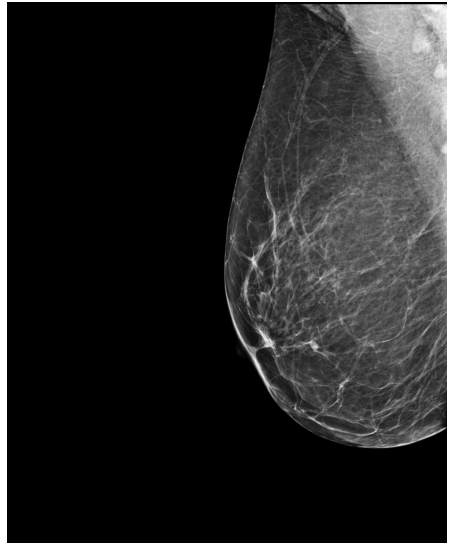

Refer to caption

(a) FeatAlign

(b) FeatAlignReg

(c) ImgFeatAlign/ImgAlign

(d) FeatAlign

(e) FeatAlignReg